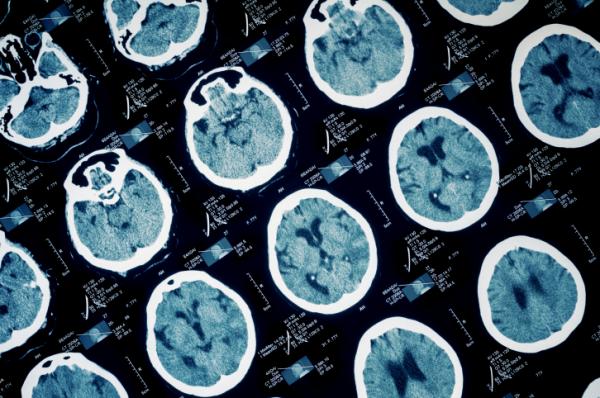

Diminuiscono le vittime di ictus nel mondo, ma aumenta il numero delle persone colpite e il peso della disabilità. E’ i risultato del primo grande studio sull’impatto dell’infarto cerebrale che tira le somme su scala planetaria, e rivela anche aspetti meno noti: nel 2010, un terzo dei casi di ictus si è verificato in persone al di sotto dei 64 anni, compresi circa 84.000 bambini e ragazzi con meno di vent’anni. Quasi tutti in paesi a reddito medio-basso. E’ quindi fondamentale ricordare come agire subito per scoprire se è in corso un attacco.

LO STUDIO – L’analisi, sostenuta dalla Bill & Melinda Gates Foundation e pubblicata su The Lancet, si è basata sui dati del Global Burden of Diseases, Injuries, and Risk Factors Study che registravano i numeri degli ictus nelle varie aree geografiche fra il 1990 e il 2010. In generale, i casi fra gli adulti sono aumentati soprattutto nei paesi a basso reddito e la mortalità è calata ovunque, anche se l’ictus resta la seconda causa di morte nel mondo. Nel 2010 si contavano 16,9 milioni di persone colpite da ictus, 33 milioni di sopravvissuti all’evento e 5,9 milioni di decessi. Di questi, la gran parte era nelle regioni meno ricche: rispettivamente il 68,9% dei casi, il 52,2% dei sopravvissuti, il 70,9% delle morti e il 77,7% dei complessivi 102 milioni di anni di vita persi a causa della malattia.

NON SOLO ANZIANI - Un evento vascolare grave come l’ictus riguarda in prevalenza la terza età. Ma non solo. Nel 2010 sono stati 5,2 milioni i casi in persone con meno di 64 anni, cioè il 31% del totale. L’89% dei bambini e ragazzi colpiti vivono in paesi a basso e medio reddito (74.000), così come il 78% degli adulti fra i 20 e i 64 anni (4 milioni). In generale, 6 casi su 10 di ictus (e il 45% dei decessi) si contano in persone con meno di 75 anni.

ISCHEMIA IN DUE TERZI DEI CASI - Un secondo lavoro apparso su The Lancet Global Health ha esaminato il fenomeno sulla base delle tipologie di ictus (ischemico ed emorragico) e degli specifici fattori di rischio. Dall’analisi di 119 studi da tutto il mondo, è emerso che nel 2010 si sono verificati poco meno di 17 milioni di ictus, 11,5 milioni di tipo ischemico (l’interruzione del flusso sanguigno ad una parte del cervello per un trombo o un embolo), 5,3 milioni di tipo emorragico (dovuto alla rottura di un’arteria cerebrale). Nonostante sia due volte meno frequente rispetto all’ischemia, l’ictus emorragico causa i tre quinti della disabilità e la metà dei decessi.